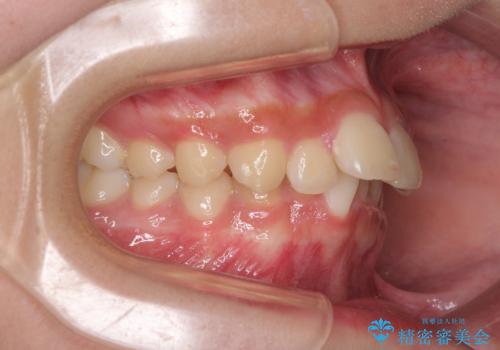

奥歯の咬み合わせを見ると、上顎が下顎に対して相対的に前方にありました。

深い咬み合わせを改善するためには、上顎臼歯を後方に移動させつつ、下顎の小臼歯を直立させる必要があります。

インビザライン単体で対応ることも検討できますが、達成する可能性が低いため、カリエールディスタライザーという補助装置を併用して、より確実性を上げることとしました。

奥歯の咬み合わせと深い咬み合わせを改善した後、インビザラインで歯列を整えることとしました。